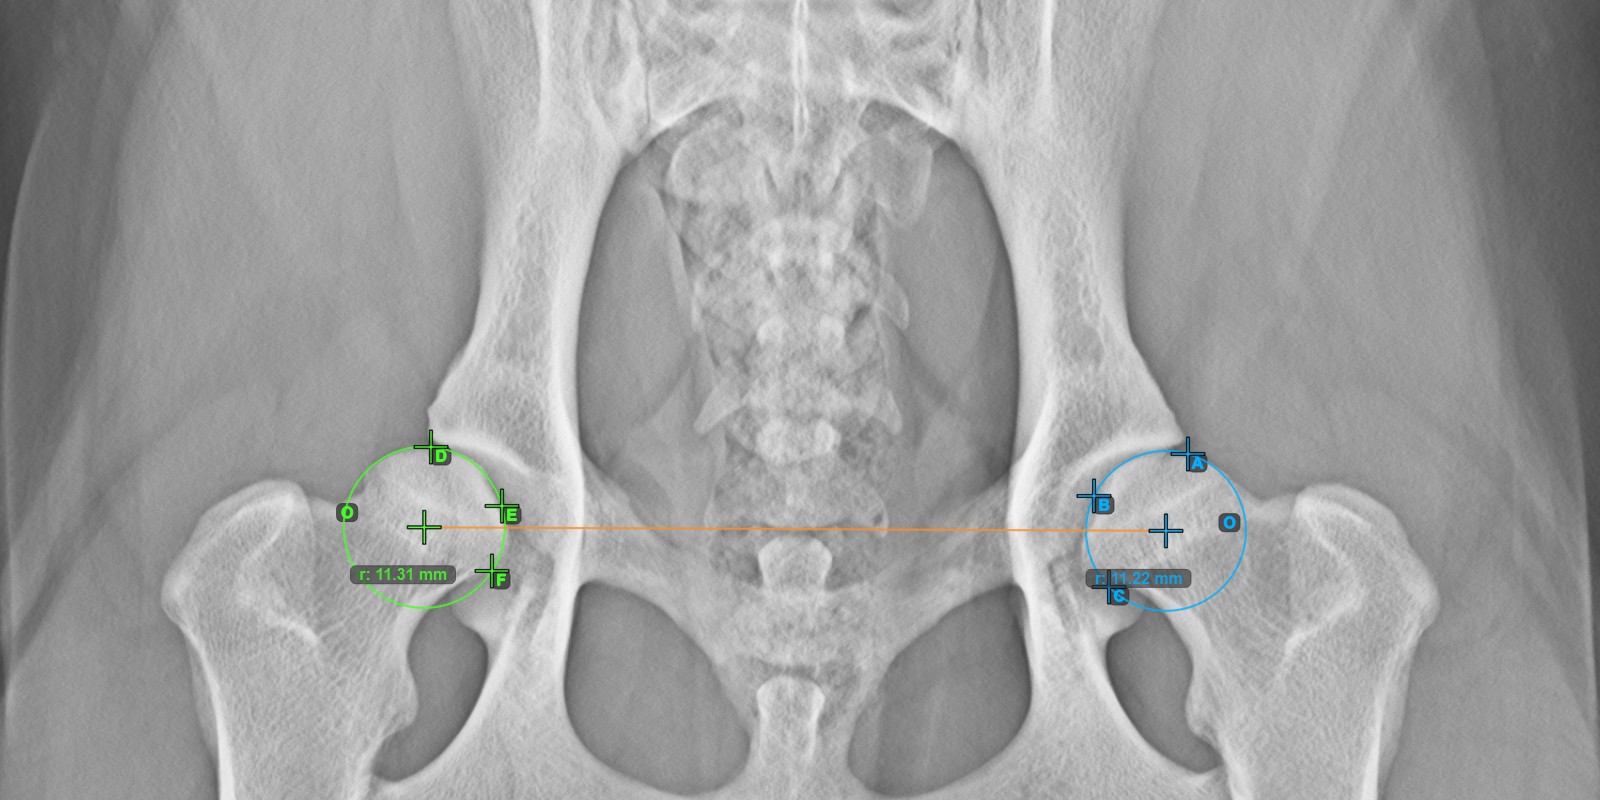

Continue by marking the three points on the articular surface of the right Caput Femoris.

Mark the three points on the articular surface of the right Caput Femoris (outside of the Fovea Capitilis). Regardless of the order, make sure to mark the most cranial point, the most caudal point and the midpoint of the femoral head. A circle will be automatically constructed based on the three placed points.

The origos of the two circles will also automatically be connected by a line, specifying the initial side of the angles yet to be constructed.

The image below depicts the typical placement of the three points on the articular surface of the right Caput Femoris.